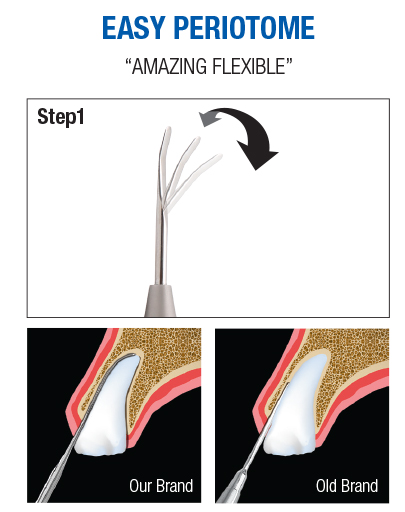

EASY PERIOTOME adopts the flexible type which can be bent freely, and ensures approach to the tooth root, so that you can cut off the periodontal ligament very easily.